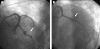

Polytetrafluoroethylene (PTFE) covered stents for the treatment of coronary artery aneurysms